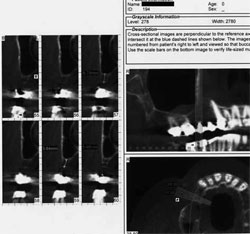

Next the patient was referred for a cone-beam tomography scan of the maxilla to evaluate the alveolar dimensions and the maxillary antra, which were thought to be inadequate (Figure 10 and Figure 11). Because radiographic studies showed maxillary sinus thickening, the patient was referred to his otolaryngologist, whose diagnosis was: "rule out ethmoid sinusitis, bilateral maxillary sinusitis with sinus cyst." Subsequent procedures were: "ethmoidectomy, bilateral revision, endoscopic, maxillary sinusotomy, endoscopic revision and ENTrak," after which the patient was cleared to proceed with sinus elevation surgery.

Cone-beam evaluation revealed approximately 5 mm of alveolar bone on the right. Because the right side demonstrated inadequate bone dimensions for simultaneous placement of implants, a lateral window sinus graft was completed first. Removing the existing bridge beforehand was not necessary because access was not impeded.13,14The lateral window-type sinus elevation was therefore performed using a combination of xenograft and allograft (Figure 12).

Figure 10 Preoperative cone-beam scan, right side. |  Figure 11 Preoperative cone-beam scan, left side. | |||||